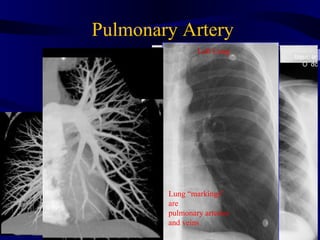

Pulmonary Artery Left Lung Coronal Image PA Lung “markings” are pulmonary arteries and veins